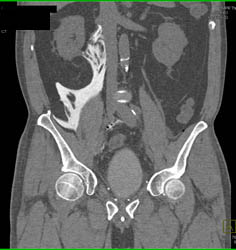

Deformed Bladder S/P Transurethral Resection of the Prostate (TURP)